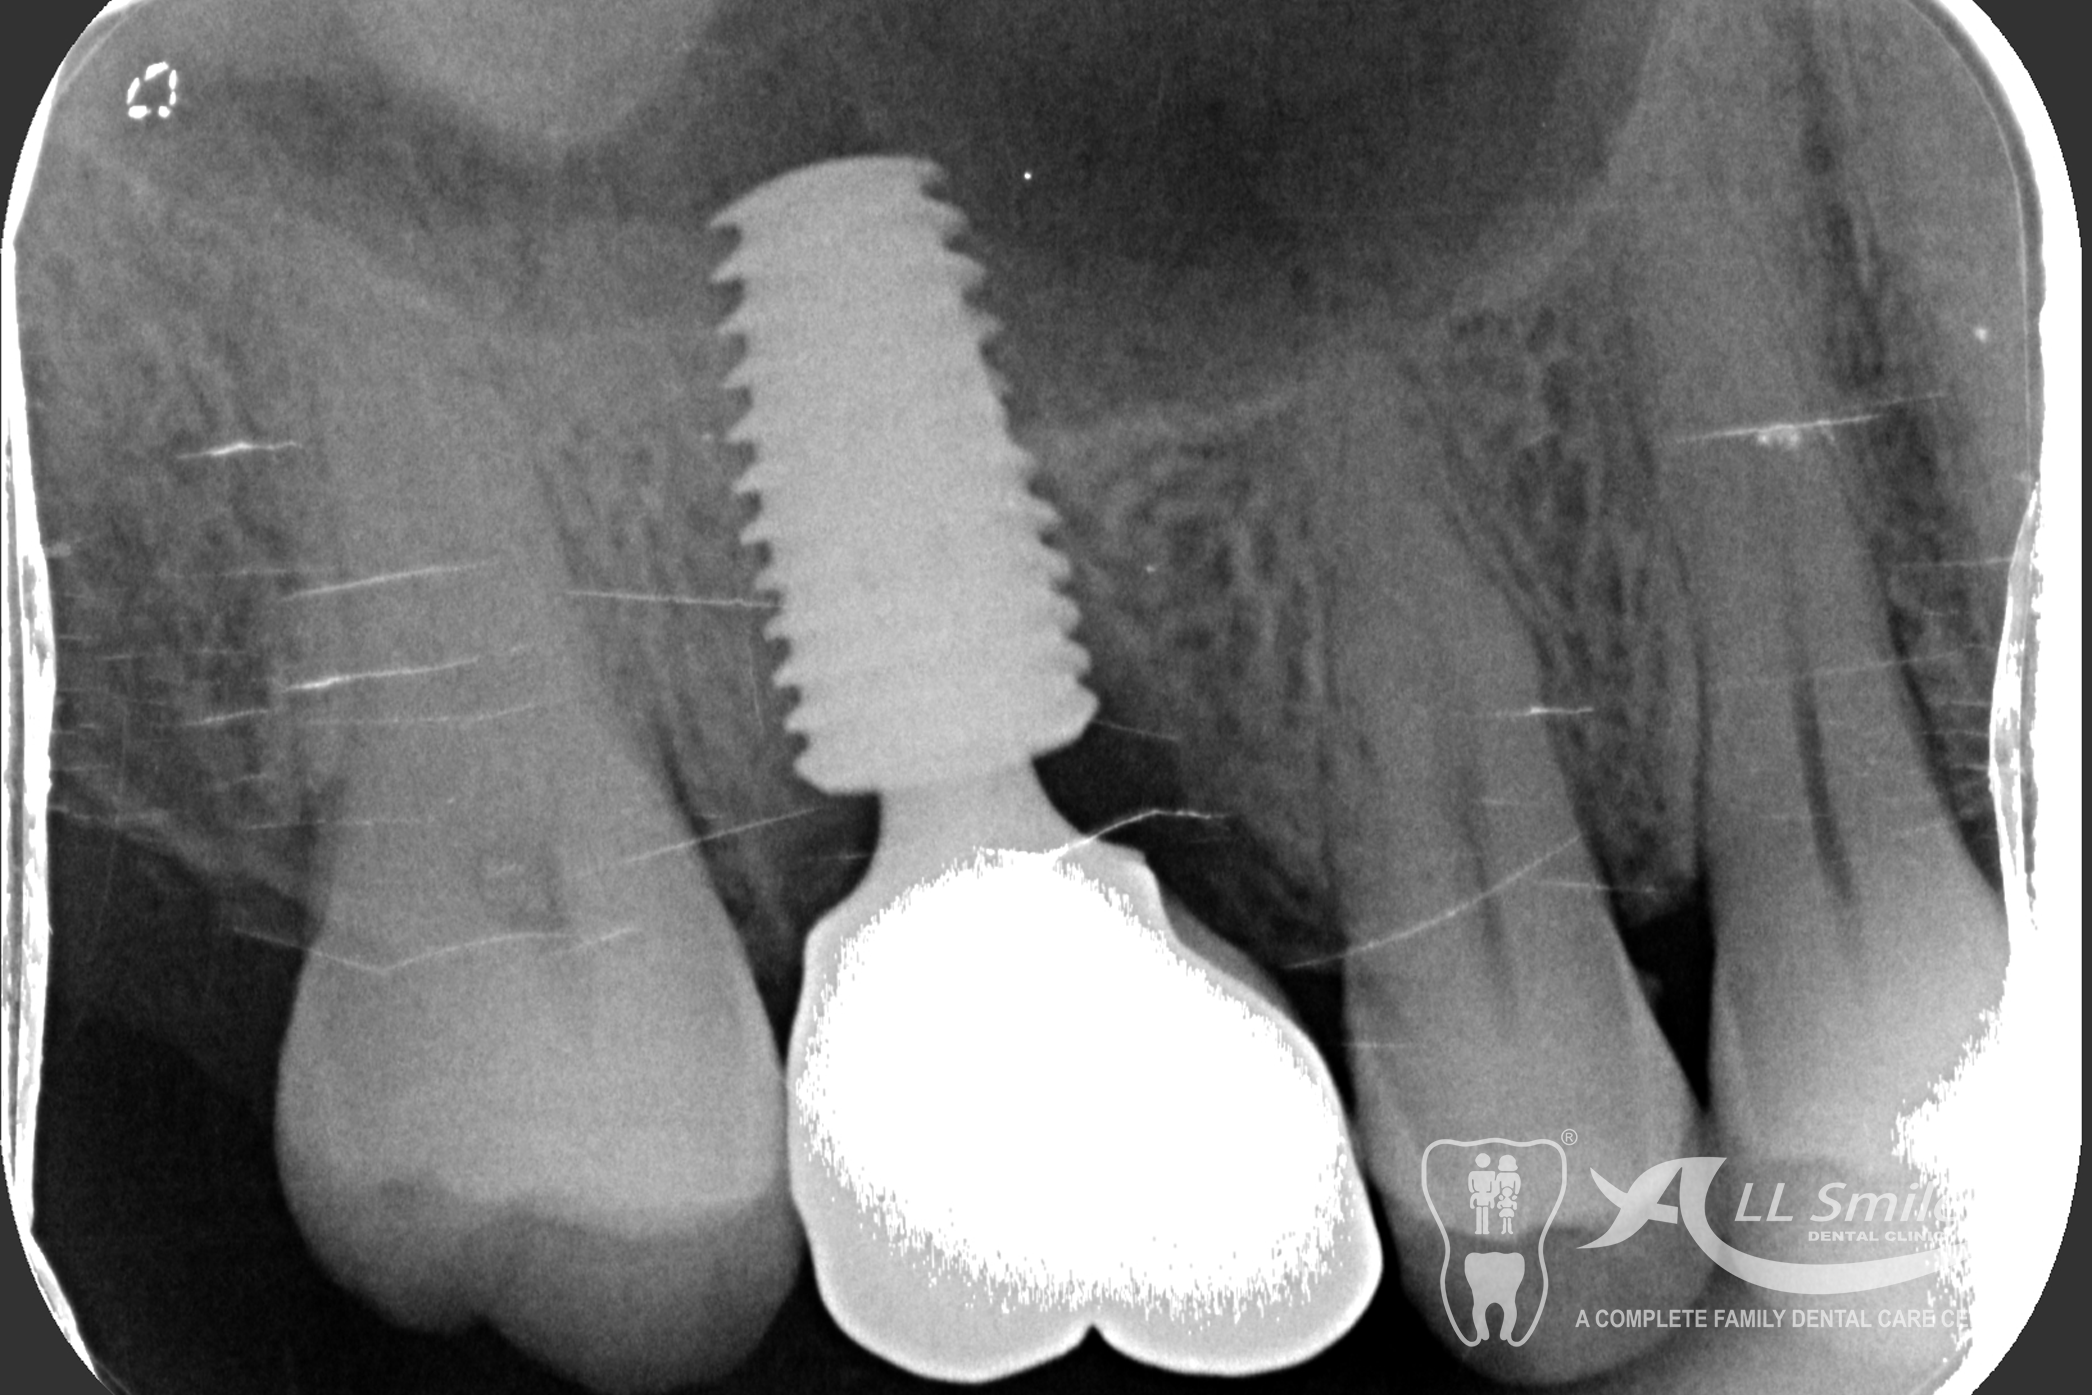

Anyone can lose a tooth. It often happens in seconds: playing sport and a tooth is gone, just like that. A shock , but no great drama any more. Implants resolve the small problem naturally and invisibly. We insert the small high-tech root at the position where the natural tooth was in the jaw.

This usually does not take any longer than any routine treatment. A temporary restoration closes the gap until the implant is healed. Then the final tooth crown is fixed in place – permanently . With the new root it is fixed firmly in the jaw and feels identical to your natural teeth.

The dental implant procedure is divided into stages. The first stage involves the placement of the implant into the jawbone, which usually takes 1-2 hours. After this, there is a healing period of 6-8 weeks during which the implant fuses with the surrounding bone tissue. Once the implant has healed, a small connector called an abutment is attached to the implant, followed by the attachment of a dental crown, bridge, or denture.